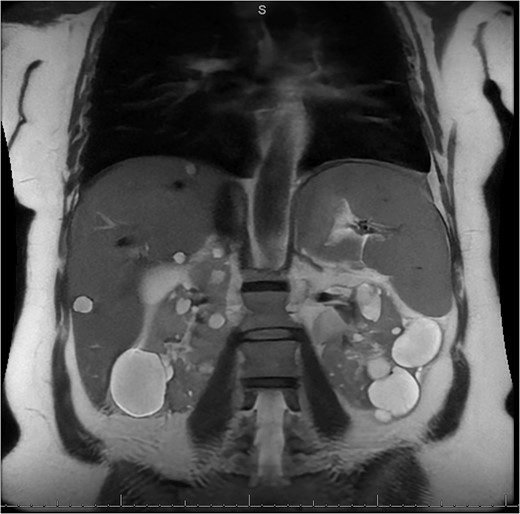

A 49-year-old female with a history of ADPKD and multiple liver cysts, 13-months status post subtotal cholecystectomy, endoscopic retrograde cholangiopancreatography with biliary sphincterotomy and balloon stone extraction, presented to the emergency department with fever and a 4-day history of discomfort in the right upper quadrant. At the time of the initial cholecystectomy, total cholecystectomy could not be performed due to extensive adhesions, and subtotal cholecystectomy with complete evacuation of the stones was done instead. Magnetic resonance cholangiopancreatography (MRCP) done at that time showed a dilated common bile duct (CBD) to 1.5 cm, intra and extrahepatic biliary dilatation, multiple liver cysts measuring up to 2 cm, and multiple stones in the CBD, including at the level of the ampulla (Fig. 1). Computerized tomography scan at the time of the second admission showed acute cholecystitis and she had mildly elevated transaminases, but there was no evidence of cholestasis or pancreatitis. MRCP showed minor proximal intrahepatic biliary dilation and cholelithiasis but no duct calculi (Figs 2–4). A laparoscopic cholecystectomy was attempted with extensive adhesiolysis between the gallbladder and surrounding omentum and mesocolon, but the cystic duct could not be isolated, and ultimately the cased was converted to open. While removing the gallbladder in a top-down fashion, a small bile leak was identified right at the closed end of the gallbladder remnant, where the bile duct was adhered to the gallbladder wall. Intraoperative cholangiogram was obtained through a small perforation in a right posterior bile duct at the site of attachment, which showed right posterior, right anterior and left hepatic ducts of equal size converged at a trifurcation (Fig. 5). The duct was repaired over a T-tube and observed throughout the rest of the case and no bile leak was identified. The gallbladder was opened along its lateral edge, revealing a hugely dilated cystic duct with ~10 to 12 marble-sized stones packed within the gallbladder remnant and cystic duct down to the juncture with the common bile duct. All the stones were removed and the safe portion of the gallbladder remnant was resected leaving the side attached to the bile duct in situ due to the Mirizzi anatomical variant. The cystic duct was oversewn along with the remnant of the gallbladder wall. Pathology showed acute-on-chronic cholecystitis with cholelithiasis. Repeat MRCP showed no retained stones in the biliary tree. The recovery course was unremarkable.

MRI/MRCP from second hospitalization demonstrating recurrent cholelithiasis.